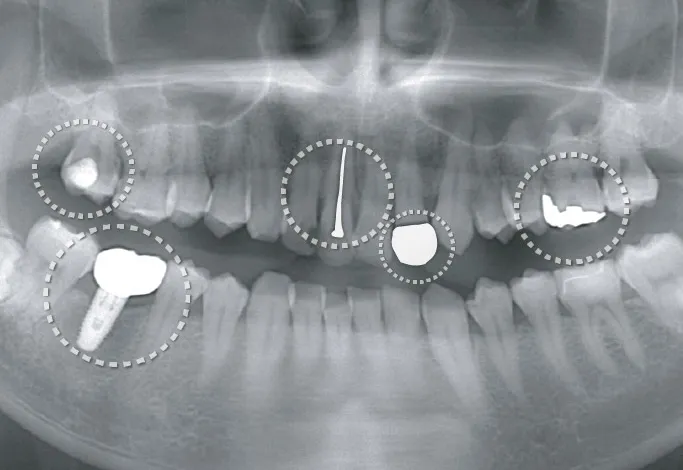

歯科の医療ホワイトニング